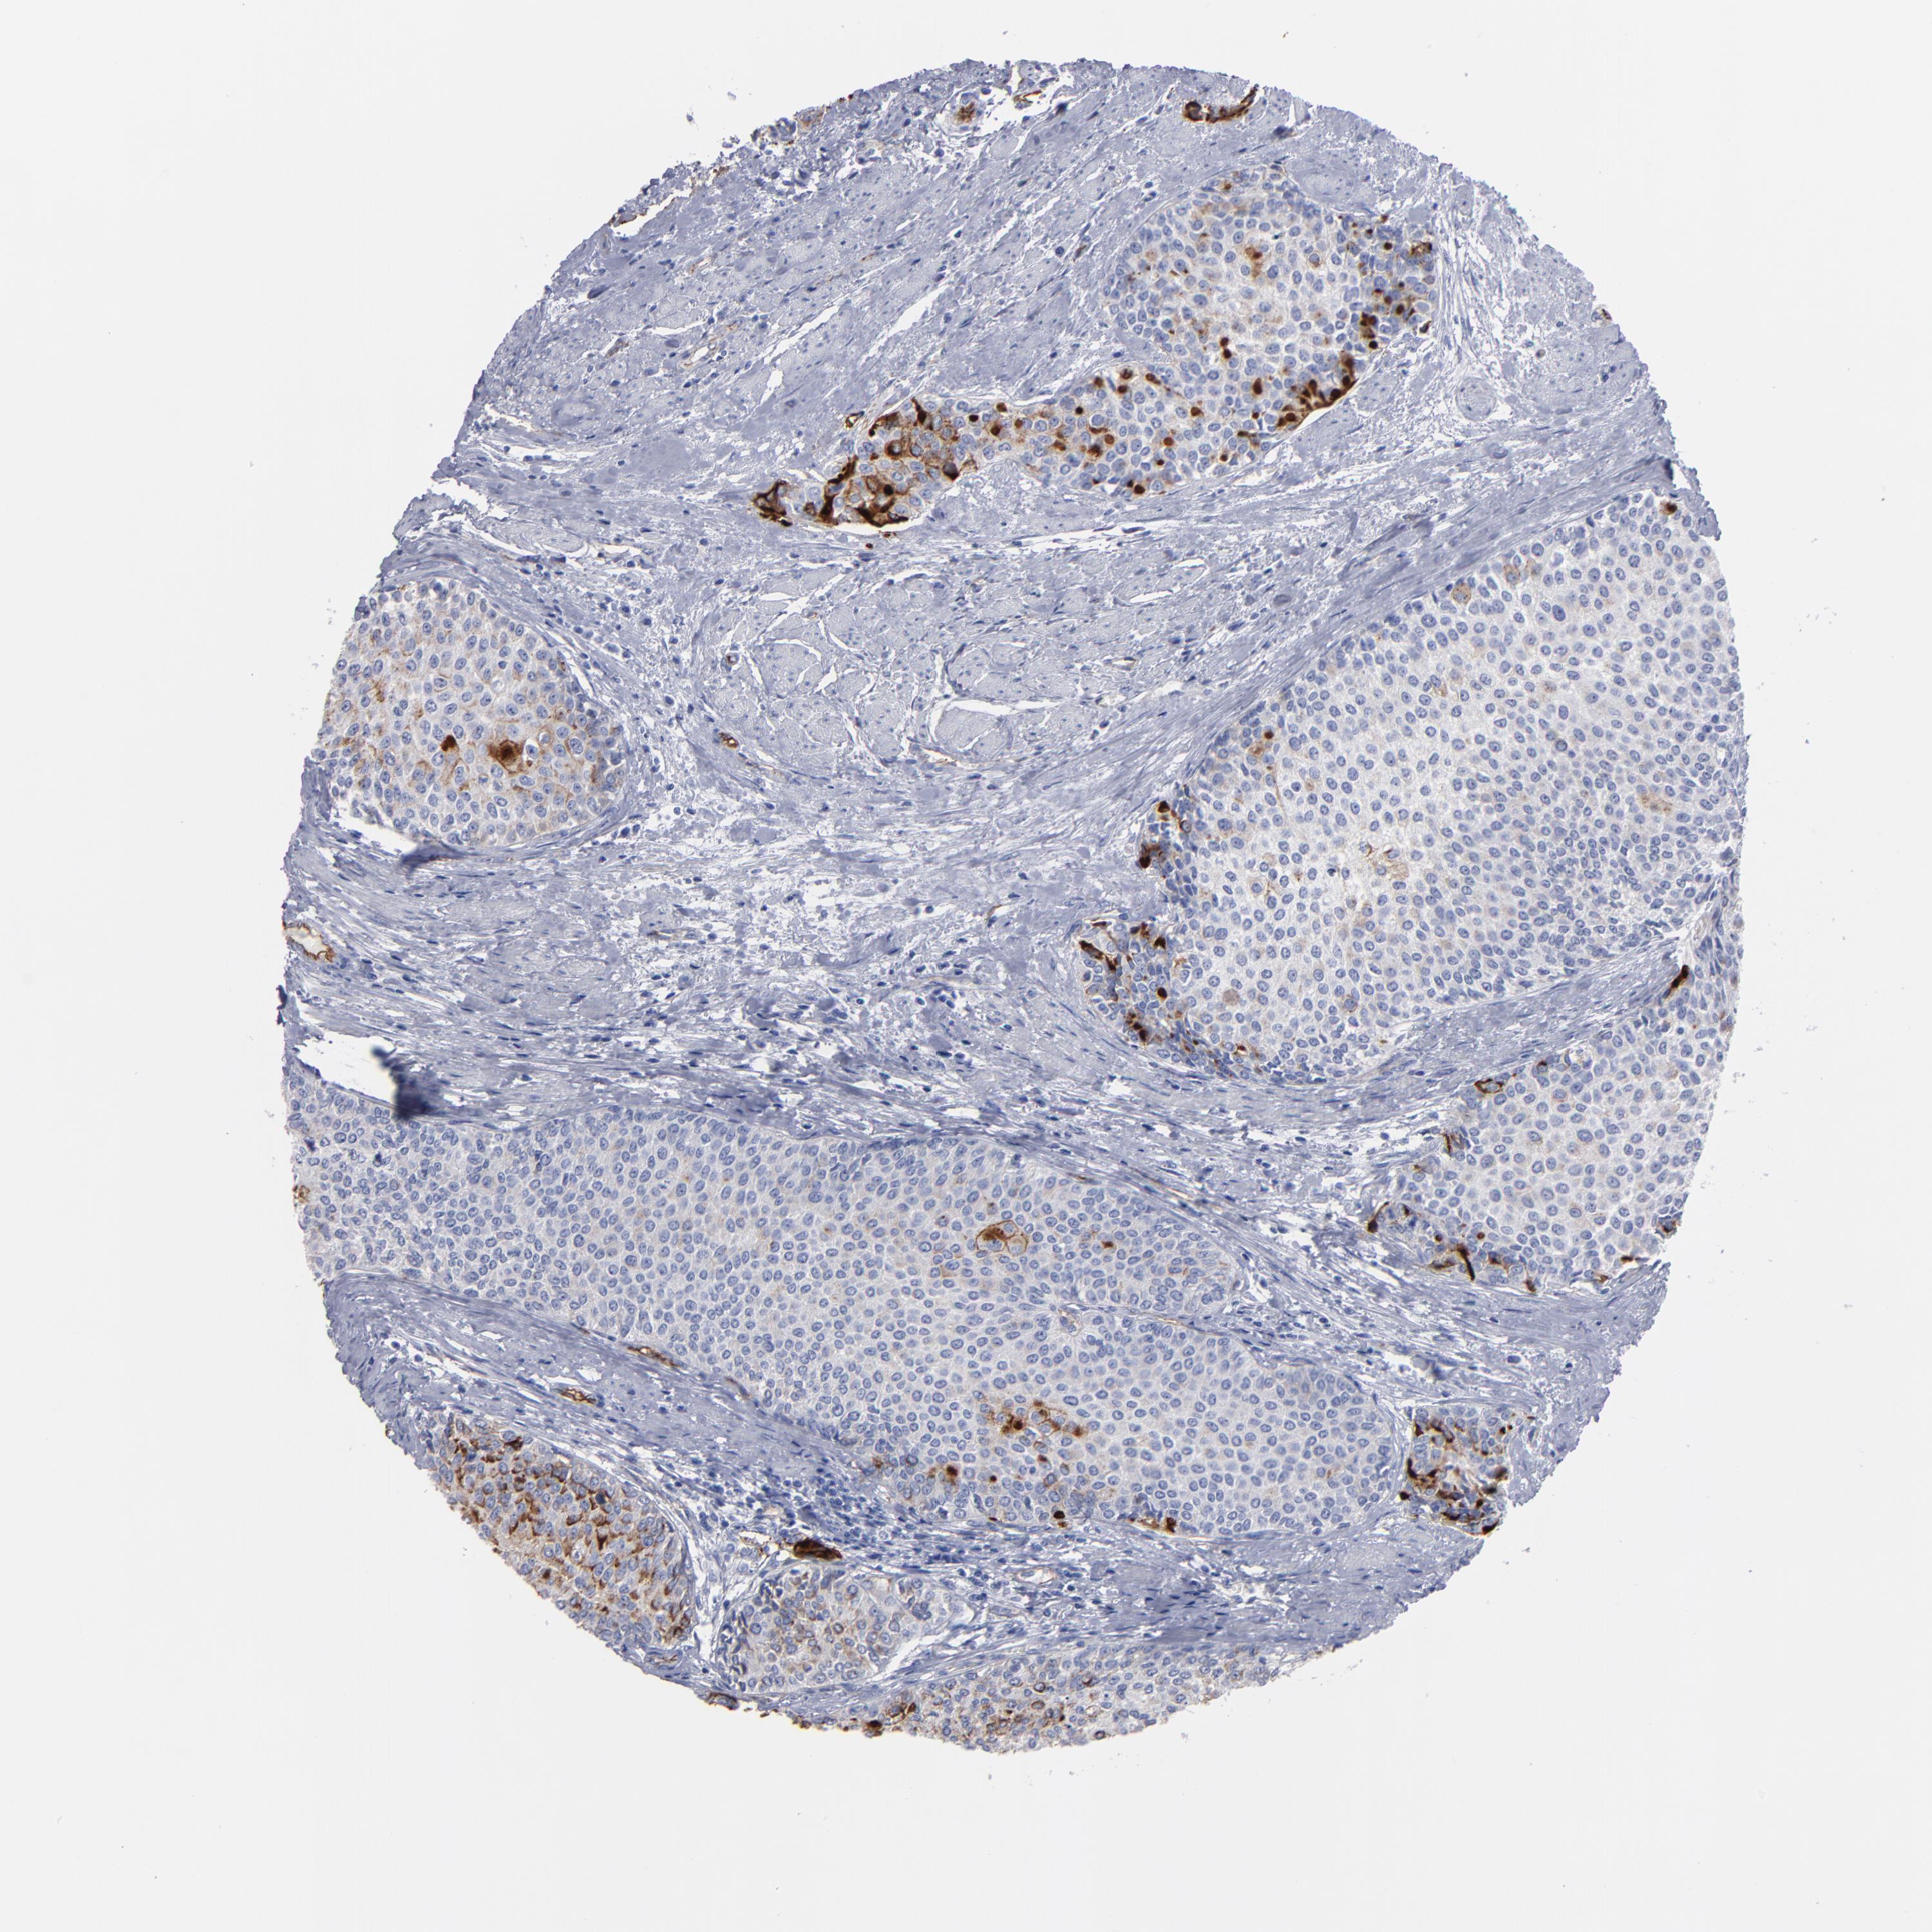

UROTHELIAL CANCER - Protein expressioni

A mouse-over function shows sample information and annotation data. Click on an image to view it in a full screen mode. Samples can be filtered based on level of antibody staining by selecting one or several of the following categories: high, medium, low and not detected. The assay and annotation is described here.

Note that samples used for immunohistochemistry by the Human Protein Atlas do not correspond to samples in the TCGA dataset.

Antibody stainingi

Antibody staining in the annotated cell types in the current human tissue is reported as not detected, low, medium, or high, based on conventional immunohistochemistry profiling in selected tissues. This score is based on the combination of the staining intensity and fraction of stained cells.

Each image is clickable and will lead to virtual microscopy that enables deeper exploration of all samples and also displays staining intensity scores, fraction scores and subcellular localization as well as patient and tissue information for each sample.

Antibody HPA002823

Antibody CAB002760

Staining

High

Medium

Low

Not detected

Intensity

Strong

Moderate

Weak

Negative

Quantity

>75%

75%-25%

<25%

None

Location

Nuclear

Cytoplasmic/membranous

Cytoplasmic/membranous,nuclear

Urothelial carcinoma, High grade

Urothelial carcinoma, Low grade

Adenocarcinoma, NOS